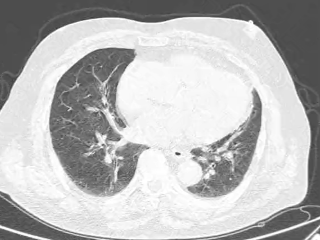

头部CT、胸部CT

患者1周前无明显诱因出现胸闷、气喘,活动后明显,夜间可间断平卧入睡,伴有头晕、头痛,严重时感眩晕,偶有腹胀,无咳嗽、咳痰,无明显头晕、头痛、黑曚、胸痛、腹痛等伴随症状,自行服用药物治疗(具体不详),效果不佳,为求进一步诊治,就诊于我院急诊科,行头颅CT、胸部CT等检查,诊断“心力衰竭肺部感染?”,以“心力衰竭 肺部感染?”收入院。